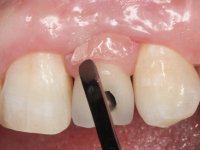

This addition of resin would guide the ceramist in the final placement of the gingival tonality ceramic. The crown that would rehabilitate tooth 1.3 was cemented in this test session with glass ionomer cement, reinforced with composite resin. Once the laboratory work was finished on the veneer for tooth 1.2, the abutment, and the veneer for the implant, this was bonded in the mouth, after placement of the absolute insulation. The work completely satisfied the patient. For eight years, the patient had periodical check-ups, and was pleased with the treatment, but also began to show interest in an aesthetical intervention on the upper central incisors. Once the second phase of our intervention was decided, dental preparation of teeth 1.1 and 2.1 was performed for the placement of two feldspathic veneers. Particular care was taken in the distal inter-proximal preparation adjacent to the abutment of the implant.

The axis of insertion of the veneer in relation to the abutment was very carefully evaluated. The feldspathic veneers were prepared in the laboratory and then bonded to the mouth after placing absolute insulation. One year later, we began our third phase of treatment, after the veneer in tooth 2.1 fractured. A dental preparation was done on the bonded veneer, seeking to extend the distal inter-proximal interface more to the palate. The objective would be to move the veneer to a more palatine contact point. Preparation of tooth 1.2 was limited to creating an insertion axis. After preparation, the total crown and laboratory veneer were bonded to the mouth. First, the crown was bonded using a relative insulation with Teflon, later the veneer was bonded after the absolute insulation placement. In the crown, I used this type of insulation to avoid the use of staples. It would be difficult to apply due to the shape and size of the tooth, and would also be aggressive to the soft tissues. After bonding procedures, the occlusal integration of the work was evaluated.